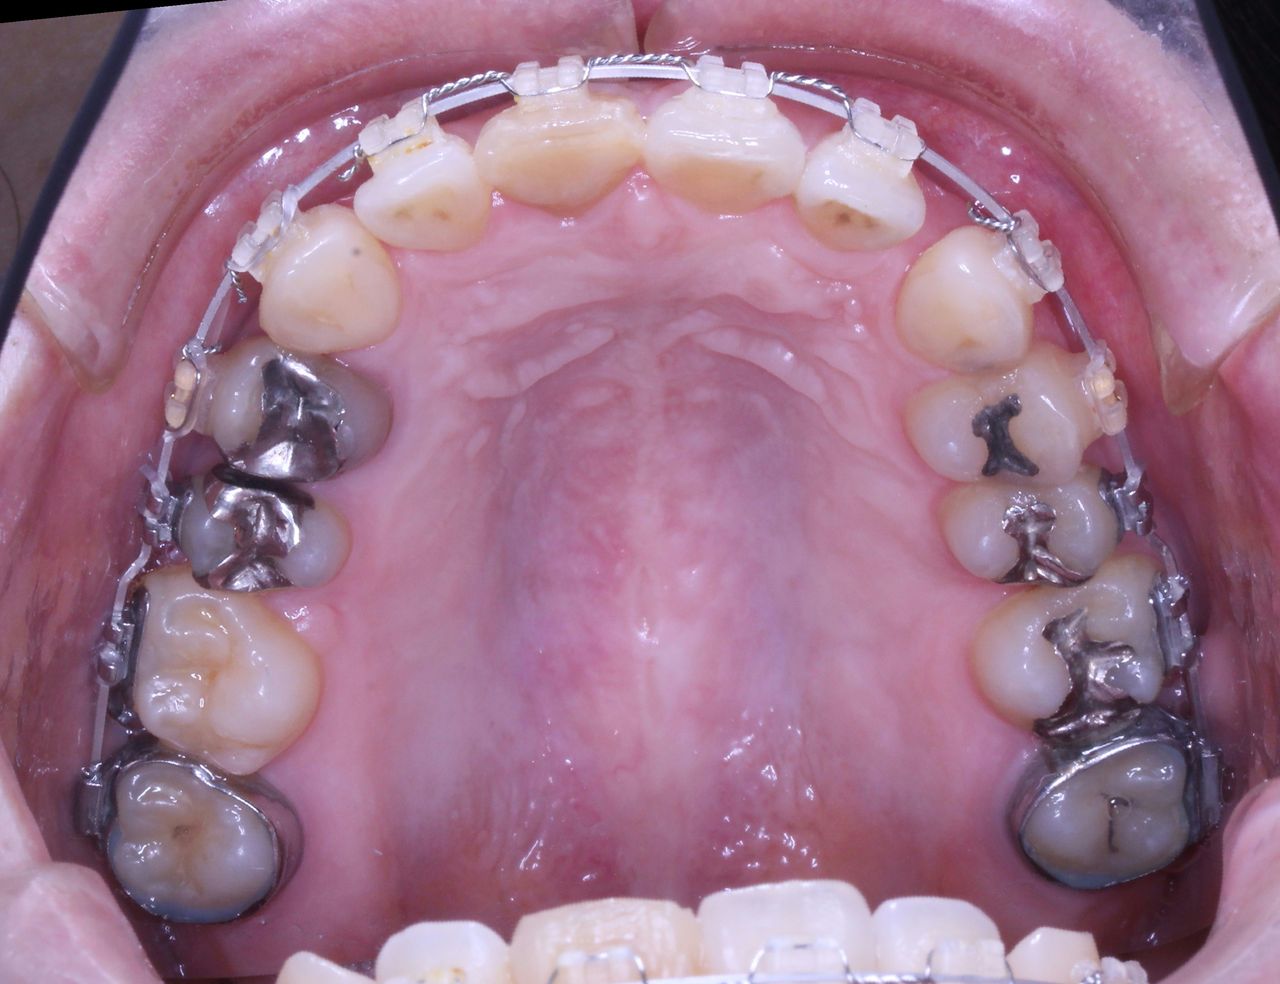

虫歯治療はきちんとされてますが、奥歯に全部銀歯の状態の歯があります。

当然、神経もない歯です。治療されたのはだいぶ前とのことでした。

それでは治療経過です